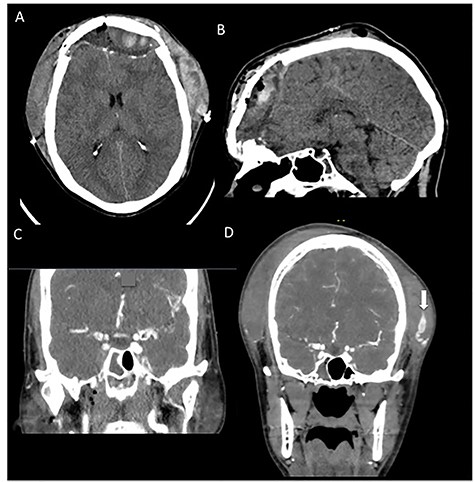

(A, B) Preoperative CT imaging showing extensive anterior and skull base fractures. The patient ultimately developed a cerebrospinal fluid leak and required operative repair. (C) Postoperative CT imaging showing bifrontal craniotomy repair as well as repair of the anterior skull base.

On hospital Day 5, the patient developed a profuse CSF leak requiring a lumbar drain was placed. Subsequently, after failure of the lumbar drain to completely stop the rhinorhea in 48 hours, the patient was taken to the operating room with both plastic surgery and neurosurgery for a bifrontal craniotomy for cranialization of the frontal sinus via split calvarial bone graft and periosteal flap. At that time he also underwent repair of naso-orbitoethmoidal fractures (Fig. 1A and C). His postoperative course was uncomplicated. On hospital Day 9 (postoperative Day 2), the lumbar drain was clamped and removed after there was no further evidence of CSF leak in 24 hours. He was ultimately discharged on hospital Day 10.